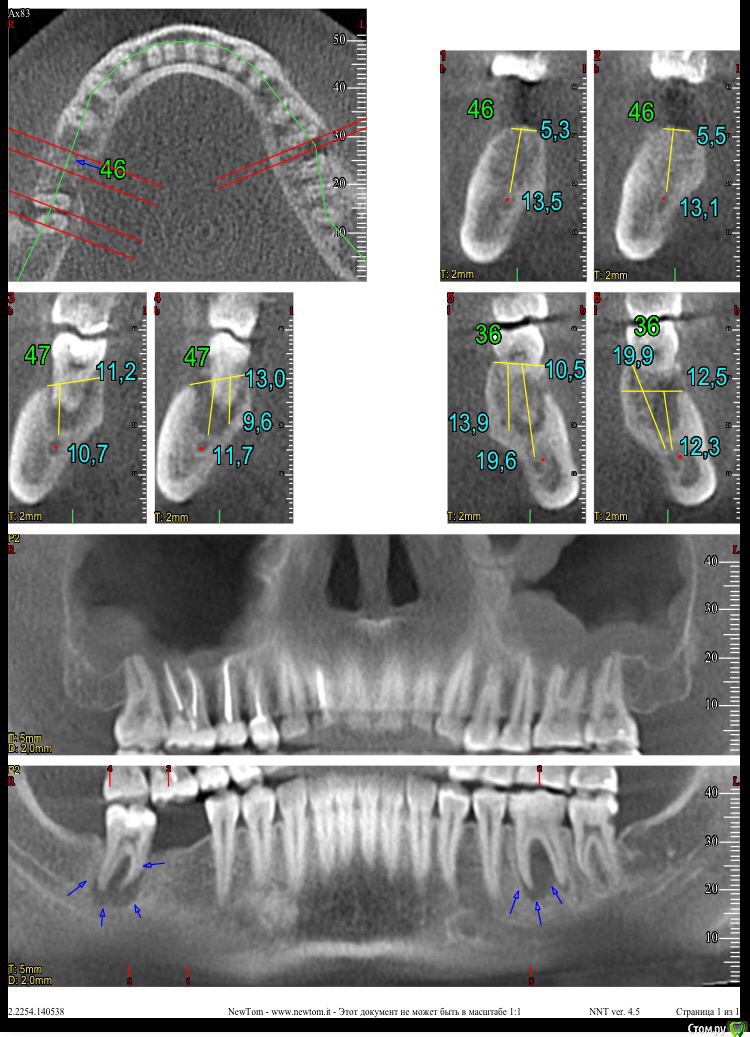

Горюшко Опубликовано 20 марта, 2015 Поделиться Опубликовано 20 марта, 2015 (изменено) Доброго времени суток! Пришла пора ставить имплант, а то затянула до этого, сделала снимок (выложу), врач сказал, что все поставит, но меня стали терзать сомнения, хотелось бы услышать Ваши мнения, советы, подсказки) Изменено 20 марта, 2015 пользователем Горюшко Ссылка на комментарий

Горюшко Опубликовано 20 марта, 2015 Автор Поделиться Опубликовано 20 марта, 2015 Какие собственно вопросы? Как мне кажется, что есть киста на двух зубах, и одна рядом с будущим имплантом, можно ли ставить в такой ситуации или придется удалять зубы, как лечить кисту, сами зубы были вылечены в январе прошлого года и поставлены накладки, их бы не хотелось убирать, можно ли как-то пролечить кисту по-другому? Ну как-то так) может еще кто увидит взглядом специалиста) Ссылка на комментарий

red_butler Опубликовано 20 марта, 2015 Поделиться Опубликовано 20 марта, 2015 1. Эндодонтическое лечение 3.6 4.7 с последующим протезированием2. имплантация в позицию 4.63. консультация ЛОР врача4. протезирование 1.6 1.5 1.4 Ссылка на комментарий

red_butler Опубликовано 21 марта, 2015 Поделиться Опубликовано 21 марта, 2015 А вот с 4 позицией не очень, а почему протезирование? зубы разрушены более 1/2 Ссылка на комментарий

red_butler Опубликовано 21 марта, 2015 Поделиться Опубликовано 21 марта, 2015 К Лору периодически хожу, вроде никаких проблем, гайморита нету. покажите Кт ЛОРу Ссылка на комментарий